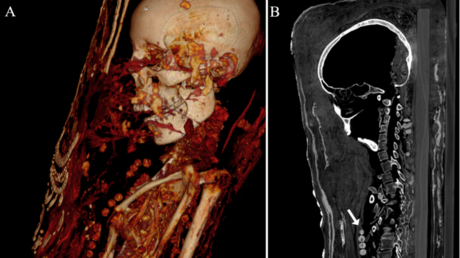

Mediante análisis de tomografía computerizada, los investigadores lograron obtener información sobre el estado de conservación de los cuerpos, la técnica de momificación artificial usada, la edad de los individuos en el momento de la muerte, así como su género, altura y salud.

Las momias, que se corresponden con un hombre adulto, una mujer de mediana edad y otra mujer joven, son las únicas cubiertas de estuco que se han encontrado en la antigua necrópolis de Saqqara. En el proceso, los cuerpos se colocaban sobre tablas de madera antes de se envueltos en tela, yeso y oro, añadiéndose en la superficie un retrato de cuerpo entero.

Además, los expertos identificaron cuentas de collares, una horquilla y objetos de metal denso, como sellos de plomo, clavos y dos monedas o medallones, con los que fueron enterrados los individuos.